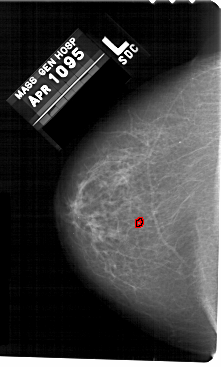

A_1479_1.RIGHT_CC

RIGHT_CC LINES 5491 PIXELS_PER_LINE 3166 BITS_PER_PIXEL 12 RESOLUTION 43.5 NON_OVERLAY

FILE: A_1479_1.LEFT_CC.OVERLAY

TOTAL_ABNORMALITIES 1

ABNORMALITY 1

LESION_TYPE CALCIFICATION TYPE PLEOMORPHIC DISTRIBUTION CLUSTERED

ASSESSMENT 4

SUBTLETY 2

PATHOLOGY BENIGN

TOTAL_OUTLINES 1

BOUNDARY